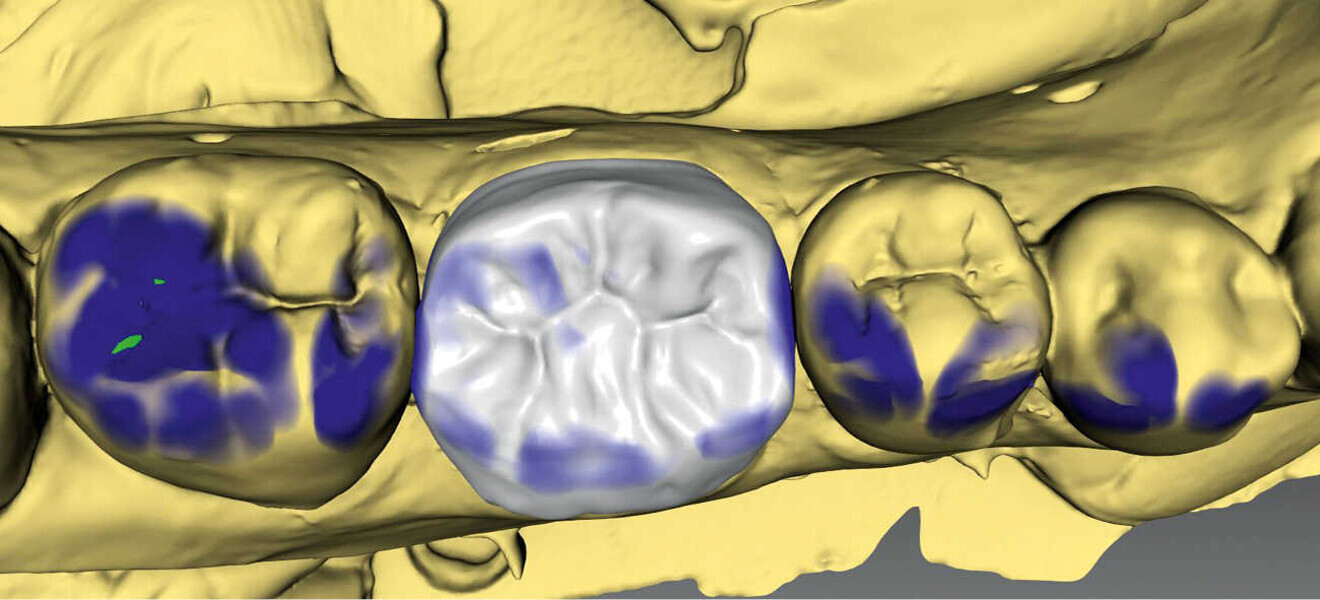

Figs. 3a & 3b. Diseño de la corona con el software (inLab) y prueba de la corona antes de la cocción de cristalización (IPS e.max CAD).